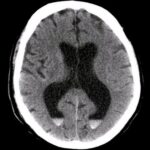

Chảy Máu Não Thất | Bài giảng CĐHA

Chảy máu não thất (intraventricular hemorrhage) nguyên phát ám chỉ đến việc chảy máu được giới hạn trong hệ thống não thất bên trong não. Chảy máu não thất nguyên phát không phổ biến, chỉ chiếm khoảng 3% tất cả các trường hợp chảy máu não. Chảy máu não thất xảy ra thường xuyên hơn trong bệnh cảnh chảy máu não hoặc chảy máu dưới nhện (chảy máu não thất thứ phát)…